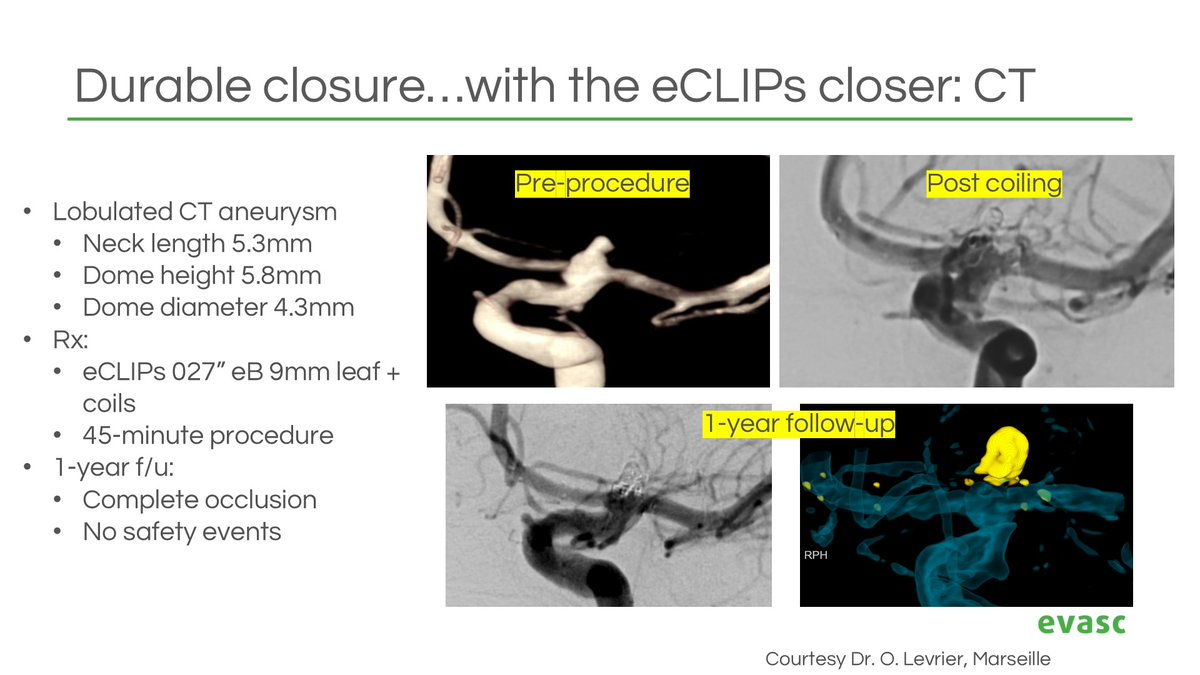

Real-world data confirm #eCLIPs delivers durable, efficient & safe outcomes for #WNBAs — now published in Neurosurgery Publications . Plus: CE/MDR approval & limited launch of our 0.021" compatible eBFD. 📄 Study: bit.ly/4lezYWp 🔗 PR: bit.ly/41oko3f #Neurointervention